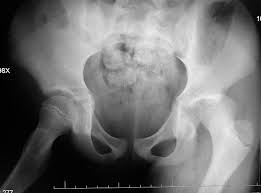

Çocuklarda kalça çıkığı, özellikle yeni doğan bebeklerde yaygın olarak görülen ortopedik bir durumdur. Kalça ekleminde femur başının (uyluk kemiği başı) kalça yuvasına tam oturmaması durumu, kalça çıkığına yol açar. Erken teşhis ve tedavi ile bu problem kontrol altına alınabilir, ancak tedavi edilmediği takdirde ciddi sağlık sorunlarına neden olabilir.

Kalça çıkığının erken teşhisi, tedavi sürecinde büyük önem taşır. Yenidoğan bebeklerde rutin kontrollerde yapılan ultrasonografi gibi görüntüleme yöntemleriyle, kalça eklemi taranarak olası anormallikler belirlenebilir. Erken teşhisle, genellikle cerrahi müdahaleye gerek kalmadan tedavi edilebilir. Pavlik bandajı gibi cihazlarla kalça eklemi stabilize edilip doğru pozisyonda tutulabilir.

Daha ileri yaşlarda veya ciddi vakalarda ise cerrahi müdahale gerekebilir. Femur başının kalça yuvasına yerleştirilmesi için yapılan cerrahi müdahaleler sonrası fizik tedavi süreci, çocuğun normal yaşantısına dönüşünü kolaylaştırır.